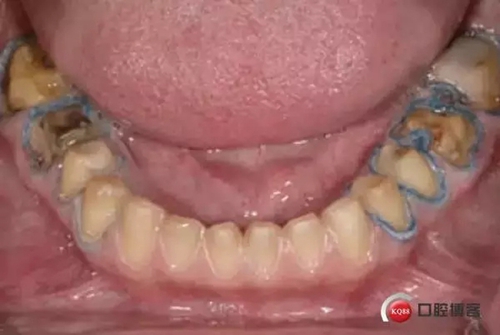

6. 輕柔的移除第二根排齦線, 第一根排齦線放置原處: 輕柔的干燥牙面,不要用力吹干。評(píng)估出血情況,水分控制情況和可見完整肩臺(tái)邊緣線。確定肩臺(tái)邊緣線是十分有必要的。

1498612936_946103.jpg